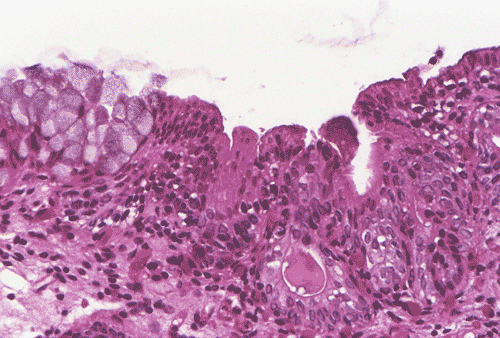

The biopsy material showed polypoid fragments with cystically dilated glands lined by columnar to cuboidal cells (Panel A, B, and C). Some of the glands were lined by transitional epithelium (Panel D), some were lined by a mixed transitional epithelium and mucin producing columnar epithelium (Panel E), and some were lined entirely by mucin producing columnar epitheliuim (Panel F) that closely resembled colonic epithelium. A mild to moderate degree of chronic inflammatory cell infiltration was also present. A mixed population of mucin producing columnar epithelium with transitional epithelium was also noted in many of the non-glandular surface epithelium (Panel G). No dysplasia was found.